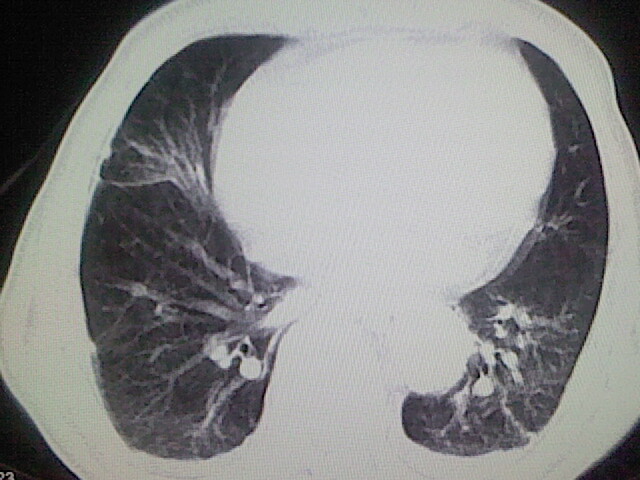

以下是引用zsl6918在2008-8-28 16:49:00的发言:[br]双肺炎性病灶,食管狭窄估计与心房增大压迫所致。

以下是引用xulianj在2008-8-28 20:36:00的发言:[br]慢支肺气肿伴感染,右上肺陈旧性结核;食道建议胃镜检查。

以下是引用wqs571018在2008-8-28 21:18:00的发言:[br]慢支继发感染,右上肺陈旧性结核;食道建议胃镜检查。